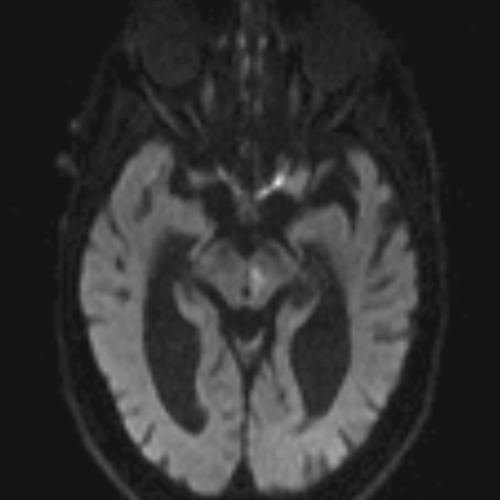

Neuro CT

250 cases

Neuro MRI

146 cases